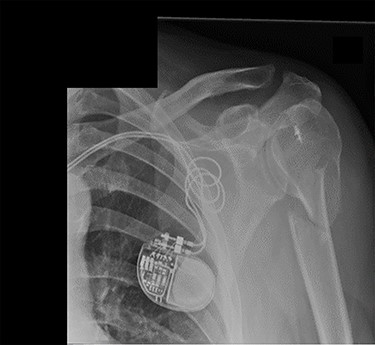

Review at 6 weeks post-injury demonstrated both clinical and radiological healing (Fig. 7). At a final 14-week review, the patient informed that he had returned to playing golf with no adverse symptoms. Examination revealed complete soft tissue healing over the fracture site and the range of movement was recorded as 120° of both abduction and forward flexion. Plain radiographs confirmed excellent fracture union, and the patient was discharged (Fig. 8).

Lateral scapula (Y) view X-ray taken 6 weeks post-injury showing radiological healing of the fracture.